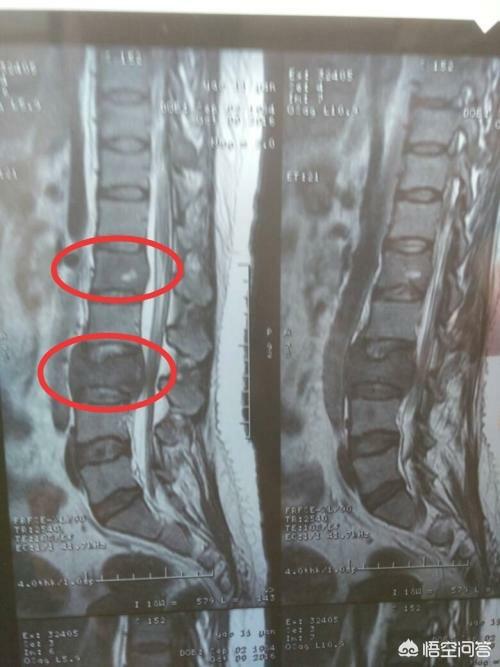

Welche Art von Schmerzen sollten auf eine Knochenmetastase hinweisen? Knochenmetastasen sind eine häufige Erscheinung bei bösartigen Tumoren im Spätstadium, d. h. der Primärtumor ist über Blut- und Lymphbahnen in andere Körperteile eingedrungen und hat dort Knochenmetastasen gebildet. Knochenmetastasen bedeuten, dass normales Knochengewebe zerstört und durch Tumorgewebe ersetzt worden ist. Knochenmetastasen lassen sich je nach Spezifität der Läsion in drei Typen einteilen: osteolytischer Typ, osteogener Typ und Mischtyp. Die häufigsten Stellen, an denen Knochenmetastasen auftreten, sind der mittlere Schaftknochen (Wirbelsäule und Becken), die Rippen und die untere Metaphyse, wobei vor allem der mittlere Schaftknochen am häufigsten betroffen ist, was mit den Eigenschaften der Blutversorgung in diesem Bereich zusammenhängt. Wie im Kreis unten dargestellt, gibt es mehrere Knochenmetastasen und die Wirbelsäule ist in einem schlechten Zustand.

Was sind die Symptome, die bei Knochenmetastasen auftreten können? Das erste Symptom ist der Schmerz. An der Stelle der Knochenmetastase treten aufgrund der Zerstörung des Knochens Schmerzen auf, die anfangs vielleicht keine offensichtlichen Symptome oder intermittierende Schmerzen haben, aber da der Tumor den normalen Knochen fortschreitend zerstört und sich allmählich verschlimmert, werden auch die Schmerzen an der metastatischen Stelle allmählich stärker. Klinisch gesehen kann es vorkommen, dass wir einen Fall von Knochenschmerzen an einer bestimmten Stelle des Körpers vorfinden, der auf eine Knochenmetastase eines bösartigen Tumors zurückzuführen ist. Vor einiger Zeit traf ich einen Fall, 40 Jahre alt, Schulterschmerzen, dachte, Schultersteife, rieb ein paar Tage der medizinischen Öl nicht sehen Verbesserung, aber mehr und mehr Schmerzen, so ins Krankenhaus zur Untersuchung, hat eine Magnetresonanztomographie, Schulterblatt wurde von einem Stück (Tumor) gegessen, unter Berücksichtigung Knochenmetastasen, und dann hat eine Brust-CT, ein Knoten in der rechten Lunge, und nahm dann eine Biopsie, um die Pathologie, die Knochenmetastasen von Lungenkrebs zu tun war. Die Informationen sind wie folgt.